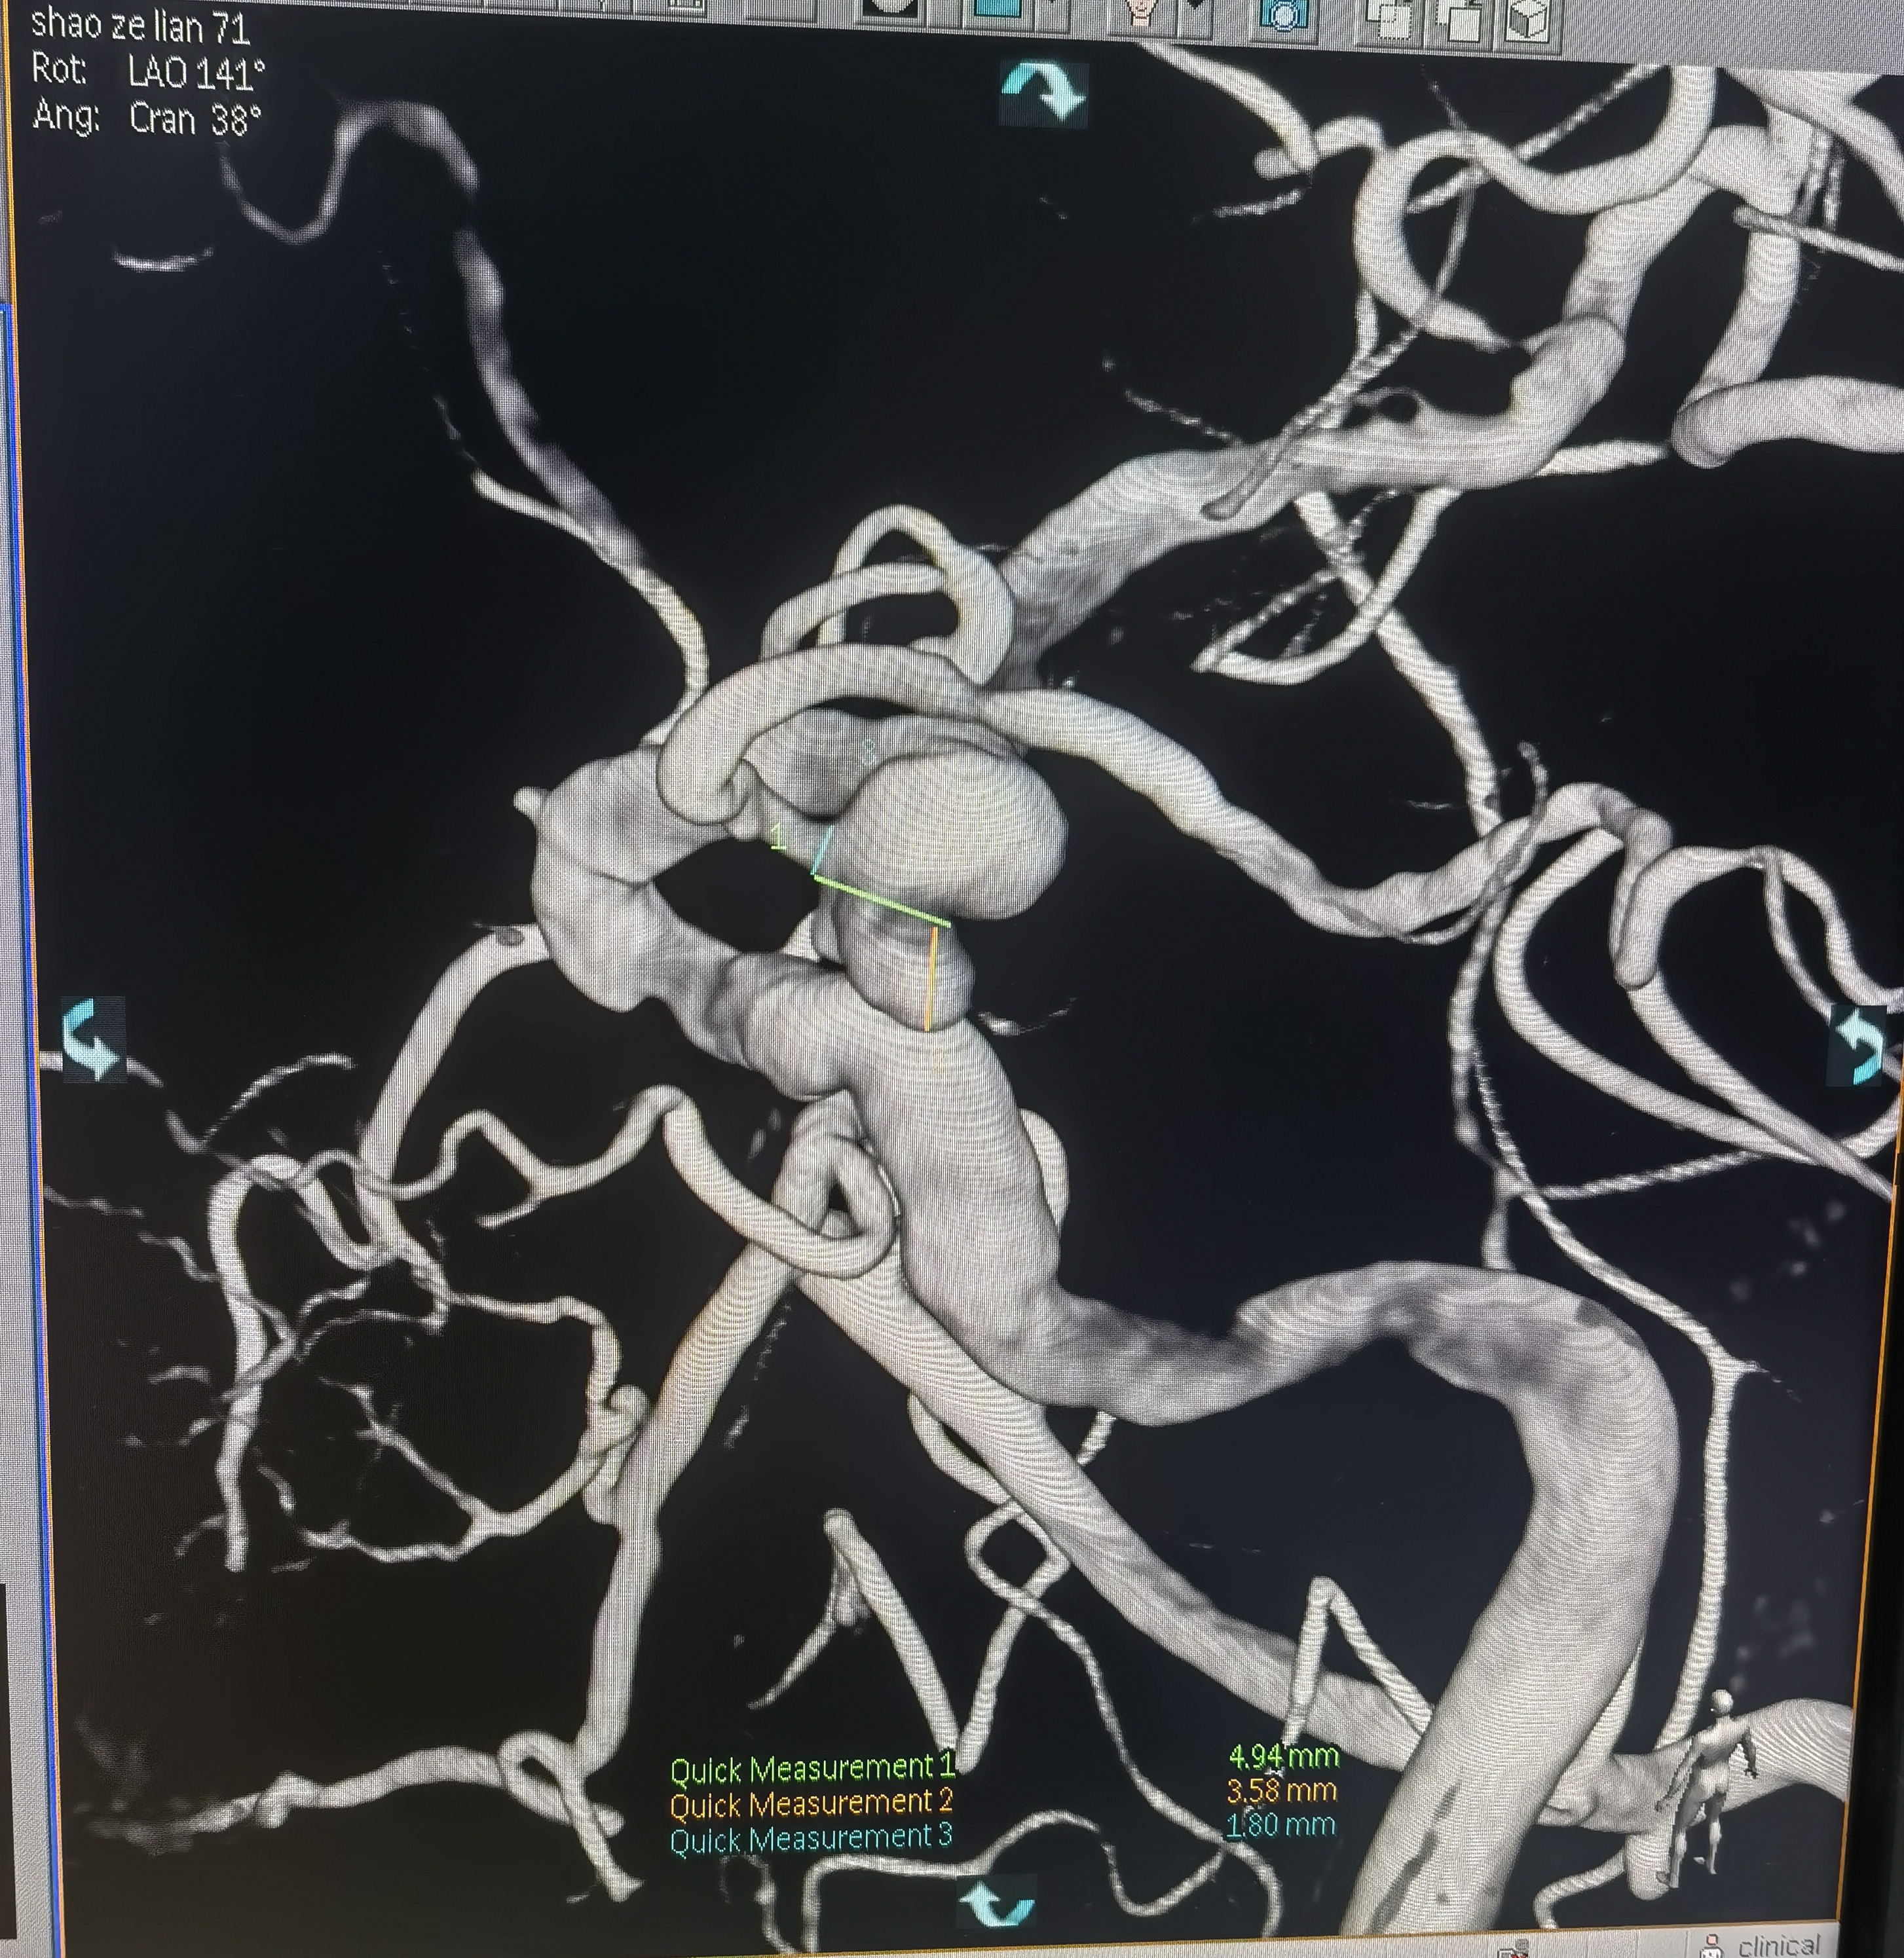

你的浏览器不支持video标签. 入院CT 血管迂曲你的浏览器不支持video标签. RCCA正位,胚胎型大脑后动脉,右侧大脑前动脉纤细。你的浏览器不支持video标签. RCCA3D造影你的浏览器不支持video标签. 右侧3D 右侧后交通动脉瘤形状亦不规则,拟二期治疗。你的浏览器不支持video标签. LCCA正位,胚胎型大脑后动脉,左侧A1供应双侧大脑前动脉。你的浏览器不支持video标签. LCCA3D造影你的浏览器不支持video标签. 左侧3D你的浏览器不支持video标签. 左椎正位,PICA以远未显影。 左侧后交通动脉瘤形状不规则,见子瘤。 拟支架辅助栓塞左侧后交通动脉瘤。 工作位路图,显示子瘤。 微导管首先超选子瘤填塞弹簧圈后,弹簧圈从子瘤脱出,遂应用支架于颈内动脉交通段释放辅助栓塞。你的浏览器不支持video标签. 术中造影你的浏览器不支持video标签. 术中造影你的浏览器不支持video标签. 术中造影你的浏览器不支持video标签. 释放支架,术中造影。你的浏览器不支持video标签. 术后造影你的浏览器不支持video标签. 术后正位你的浏览器不支持video标签. 术后侧位